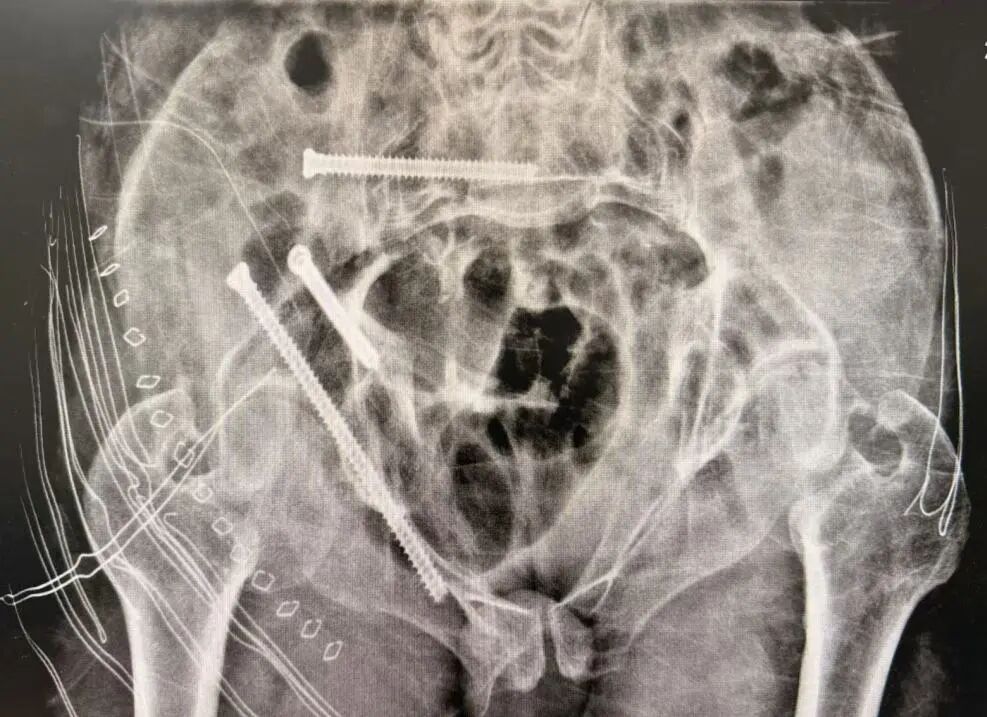

术后

术后患者恢复迅速,第二天已能下床站立。整个过程真正做到了“快、准、稳”,极大提升了手术安全性与疗效可控性。